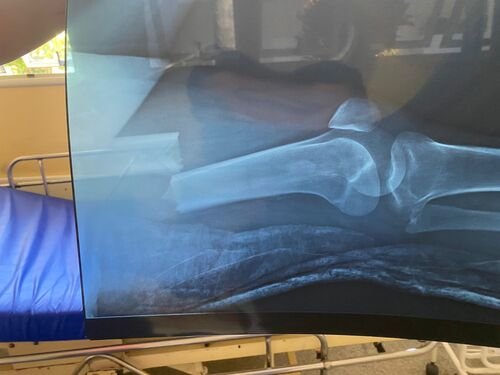

Infelizmente, ele sofreu um acidente de carro que, além de tirar sua fonte de renda, deixou sua esposa com o fêmur quebrado, precisando de cuidados médicos.